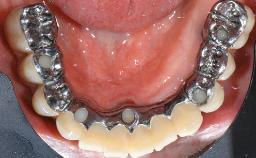

This case describes the ongoing management of a 64-year-old healthy, non-smoking female patient with erosive oral lichen planus (OLP) affecting the gingivae and the buccal and lingual mucosa. The peri-implant mucosa was also affected subsequent to implant placement. The patient had osseointegrated implants (four in the maxilla, four in the mandible) placed following extraction of hopeless teeth and a healing period. The patient had a history of OLP prior to implant placement and had been referred to an oral-medicine specialist for definitive diagnosis and treatment. She exhibited generalized oral mucosal involvement. Following a clinical assessment, biopsy, and blood tests, she was treated with topical corticosteroids. Systemic prednisolone was reserved for severe flare-ups. Amphotericin lozenges were used in combination with corticosteroid treatment to prevent the development of oral candidiasis.

# of Implants 8

Type of Implants Two-Piece

Prosthesis Type FDP

Retention Screw-retained, with 4 or more splinted implants Screw-retained, with 4 or more splinted implants